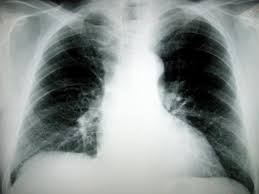

Cigarette smoking is a leading cause of COPD, a slowly progressive disease of the lung that is characterized by a gradual loss of lung function. COPD is the fourth most common and the most rapidly increasing cause of death in the United States. Emphysema, chronic bronchitis, chronic obstructive bronchitis, or a combination of emphysema and chronic bronchitis are forms of COPD.